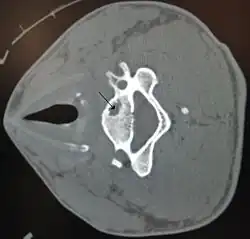

A bone cyst in the vertebra of the neck as seen on CT | |

A bone cyst or geode is a cyst that forms in bone.